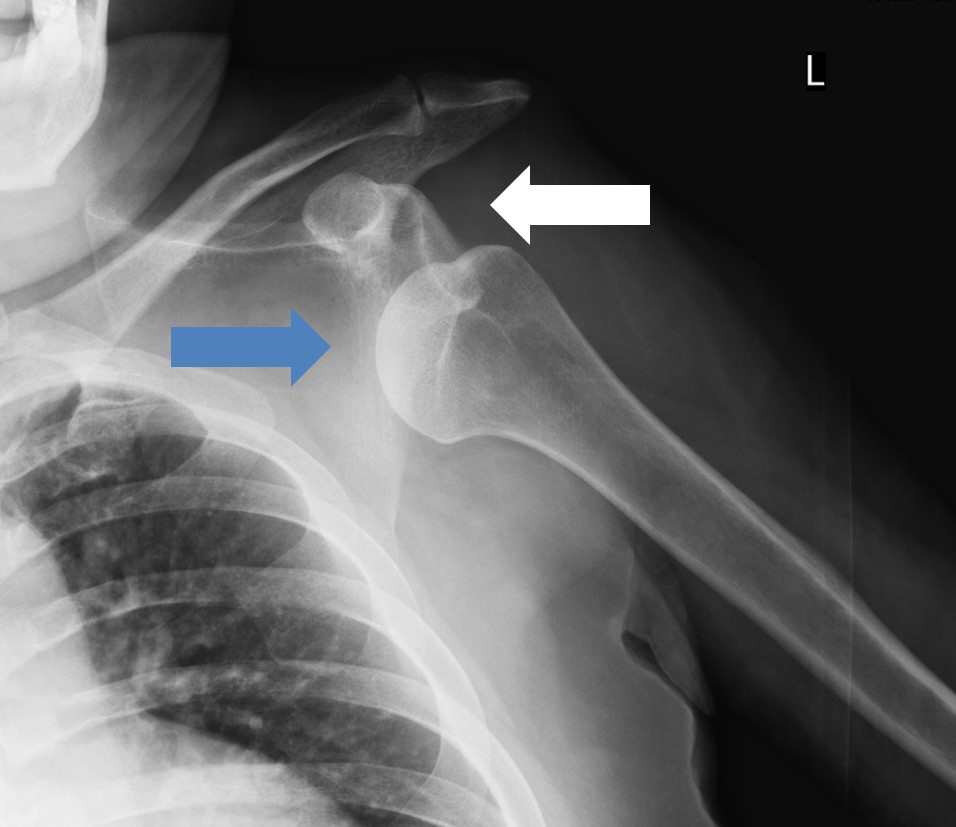

裁断済み】 肩関節のMRI 第3版 - 健康・医学 - 健康・医学。肩関節のMRI−読影ポイントと新しい知見−第3版 | 佐志 隆士。春日クリニック】MRI画像で見る肩関節 - YouTube。Kokuu グルテンフリー雑穀300g2袋。第42回日本磁気共鳴医学会大会/肩関節腱板の小さな断裂の診断。m3電子書籍 | 肩関節のMRI 第3版。腱板断裂【肩関節外科】 | おおさかグローバル整形外科病院。傷、折れなど細かな破損を気にされる方はご遠慮下さい。凍結肩の MRI所見 : 整形外科医のブログ。その腱板断裂、ホントに交通事故の後遺症?:日経メディカル。肩関節脱臼|SPORTS MEDICINE LIBRARY|ザムスト(ZAMST)。右肩腱板断裂 いしもと整形外科リハビリクリニック - 【公式。裁断済みの為全体的に状態が悪いとしてあります。素人目での判断ですが、スキャンして使用する分には問題ありません。肩関節疾患について(2)~治療方針~ - 医療法人相生会 福岡。その他検査(関節・軟骨) 肩MRI | AIC八重洲クリニック。書き込み、マーカーはありません。